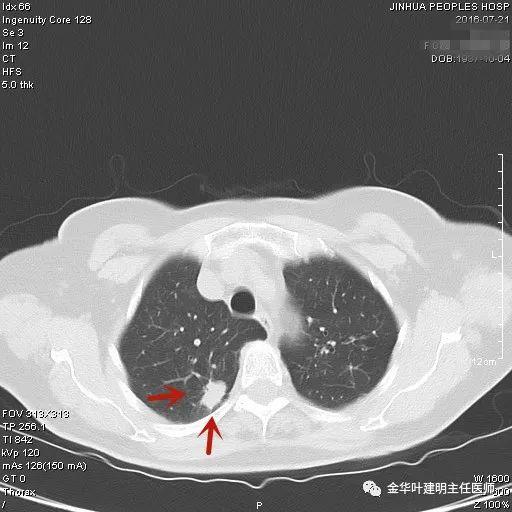

上图示慢性炎结节。我们见其桔色箭头示长毛刺征,绿色箭头示有血管贴边,但进出病灶的血管粗细相对没有什么改变(说明没有被病灶窃取多少血供),整体病灶边缘偏模糊。